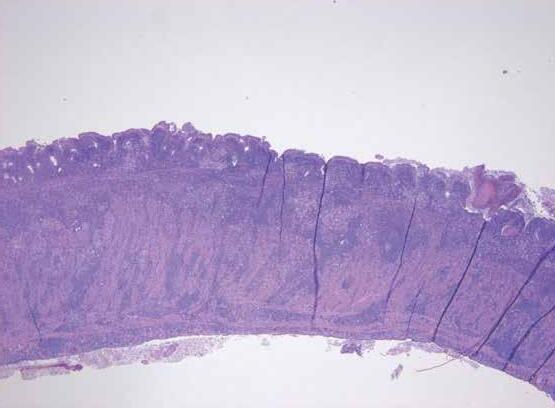

Issuu converts static files into: digital portfolios, online yearbooks, online catalogs, digital photo albums and more. Sign up and create your flipbook.